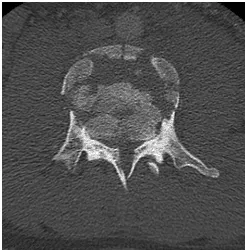

18 yo fell from 3 floors. Near complete loss of all neurological functions below the level of injury with near complete involvement of bowel and bladder

Patient was operated and the spinal canal cleaned up of all bony fragments. The spine was fixed from the side and the back to take care of instability.